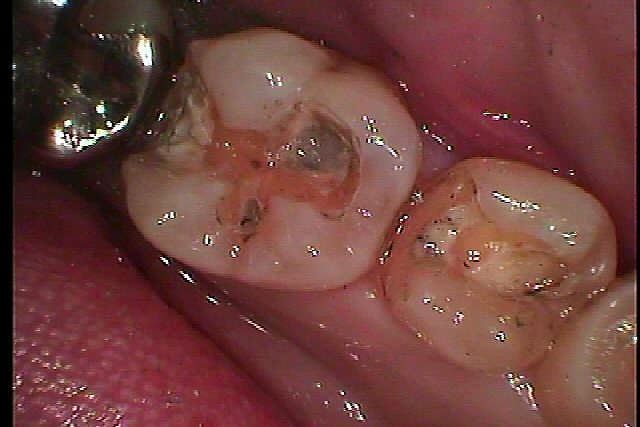

左下5,6番の銀歯を白いセラミックへやり変えていきます |お知らせ |広島市安佐南区の歯科医院 左下5,6番の銀歯を白いセラミックへやり変えていきます トップ お知らせ・ブログ お知らせ 左下5,6番の銀歯を白いセラミックへやり変えていきます 左下5,6番の銀歯を白いセラミックへやり変えていきます この銀歯を外していきます 銀歯をはずすと所々に虫歯が認められます 遠心部に大きく虫歯があります 隣接部にも虫歯が存在しています 虫歯を除去していきました CR樹脂にて覆罩を行っています セレックセラミックにてきれいなセラミックが入りました Web診療予約 初めての方へ 選ばれ続ける理由 院内設備について 歯が痛いしみる一般歯科 歯がぐらぐらする歯周病 健康な歯を保ちたい予防歯科 子供の虫歯予防をしたい小児歯科 銀歯をセラミックに審美歯科 白い歯を目指しませんか?ホワイトニング 矯正専門医がいるので安心矯正歯科 抜けた歯を補いたいインプラント・入れ歯 医院案内 スタッフ紹介 メリィハウス歯科クリニックオフィシャルホームページ ラベンダー歯科クリニックオフィシャルホームページ お知らせ・ブログ ホーム 診療科目 一般歯科 歯周病治療 予防治療 小児歯科 審美治療 ホワイトニング 矯正歯科 入れ歯・インプラント マウスピース矯正 初めての方へ 院長・スタッフ 設備紹介 医院案内・アクセス メニューを閉じる